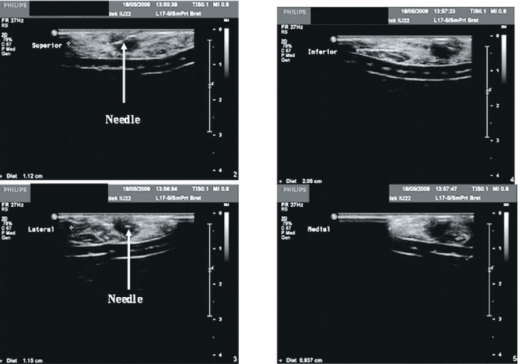

שימוש בסונר מאפשר הערכה של רוחב השוליים מיד לאחר הכריתה על שולחן הניתוחים (תמונה מספר 2). מנתח יכול לרכוש בקלות את הכישורים הדרושים להפעלת סונר תוך ניתוחי, בכריתת גידולים הניתנים למישוש, ולהגיע לתוצאה מיטבית לאחר עקומת למידה של שני ניתוחים בלבד[28].

אחת הבעיות המוכרות במהלך הניתוח היא בעיית הסימון, בין אם מדובר בציור על גבי העור, ובין אם מדובר במחט סימון. ברגע שהעור נחתך, נחתכות גם הרצועות על שם Cooper (סיבי התמיכה המעניקים לשד את צורתו הזקופה), והקשר בין החלקים השונים של הרקמה נעלם. חשיבות הסונר התוך ניתוחי היא בהדמיית הגידול בחדר הניתוח המאפשרת למנתח לתכנן את החתך הניתוחי. זהו כלי עזר המסייע למנתח בתכנון המשך מהלך הניתוח (תמונה מספר 3, תמונה מספר 4) [35].

בתום הכריתה, עם הוצאת הגוש ורקמת השד שנכרתה סביבו, יכול המנתח להעריך את מרחק החתך הכירורגי מהגוש הגידולי, ולהחליט האם יש צורך בכריתה נוספת של שוליים. כריתת השוליים נעשית באותו הניתוח, מה שככל הנראה מוביל לתוצאה מדויקת יותר מאשר ניתוח חוזר הנעשה עקב שוליים נגועים המתגלים בהערכה פתולוגית. בהסתמך על המחקר בתחום, על מנת לקבל תוצאה מיטבית יש לוודא כי המרחק הנמדד בסונר יהיה מעל 0.5 סנטימטר[32]. בבדיקה לאחר הוצאת התכשיר, ניתן להרחיב את הכריתה בכיוונים הרצויים לפי בדיקת הסונר החוץ-גופית, באופן מדויק יותר מאשר בניתוח חוזר עקב שוליים נגועים. ניתן לתעד את המדידות בהפניה לבדיקה הפתולוגית, המחייבת התייחסות מצד הפתולוגים לשולי הכריתה, בדוח הפתולוגי הסופי (תמונה מספר 5).